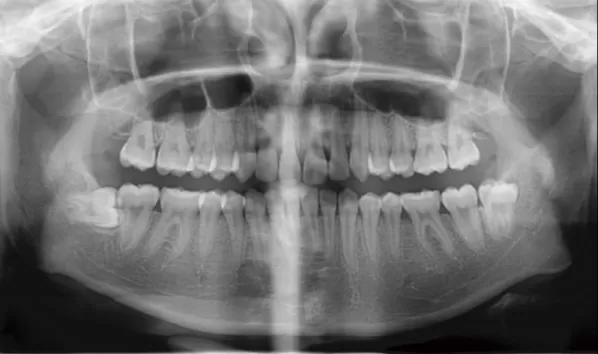

X-rays before treatment

[Panoramic Radiography/Lateral Cephalogram]